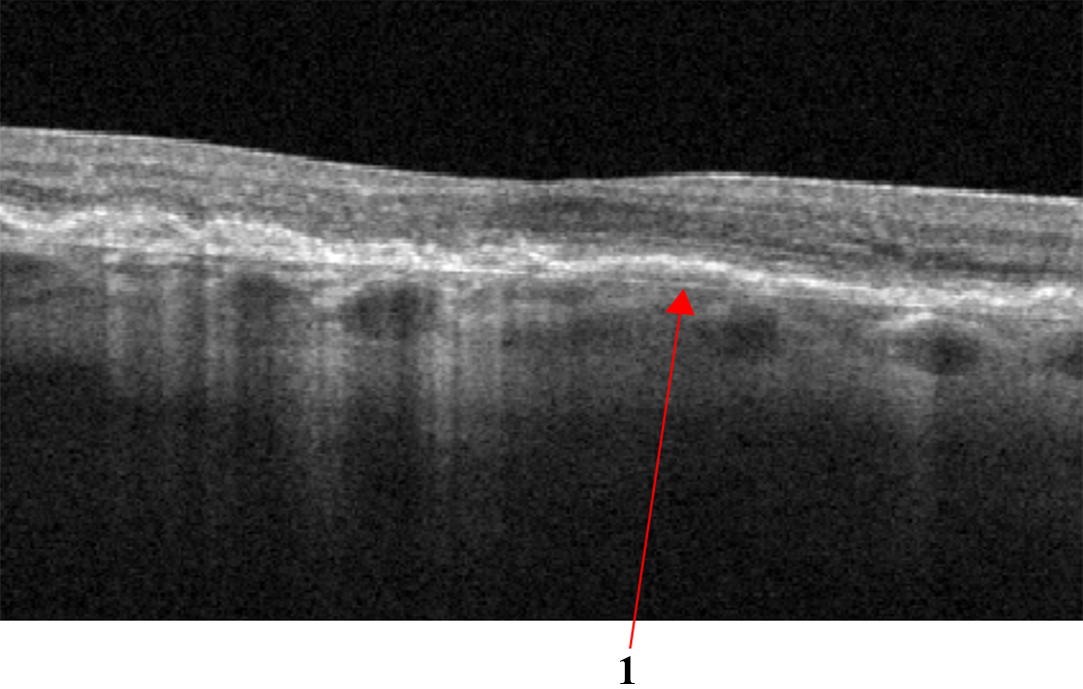

DRIL is an OCT biomarker, indicating poor definition of the boundaries of the inner retinal layers - in Fig.4b, DRIL is indicated by number 1. DRIL occurs in patients with various retinal vascular diseases with prolonged presence of intraretinal fluid, such as DME, or following a vascular occlusion, such as RVO. The degree of DRIL indicates the severity of the disease and correlates with the patient’s visual acuity prognosis. DRIL may persist even after the resolution of edema following treatment or in advanced stages of the disease [34].

Figure 4: (a) Signs of Diabetic Macular Edema (DME): 1 - Hard exudates (HE), 2 - Intraretinal fluid (IRF), 3 - Hyperreflective foci; (b) Disorganization of retinal inner layers (DRIL).